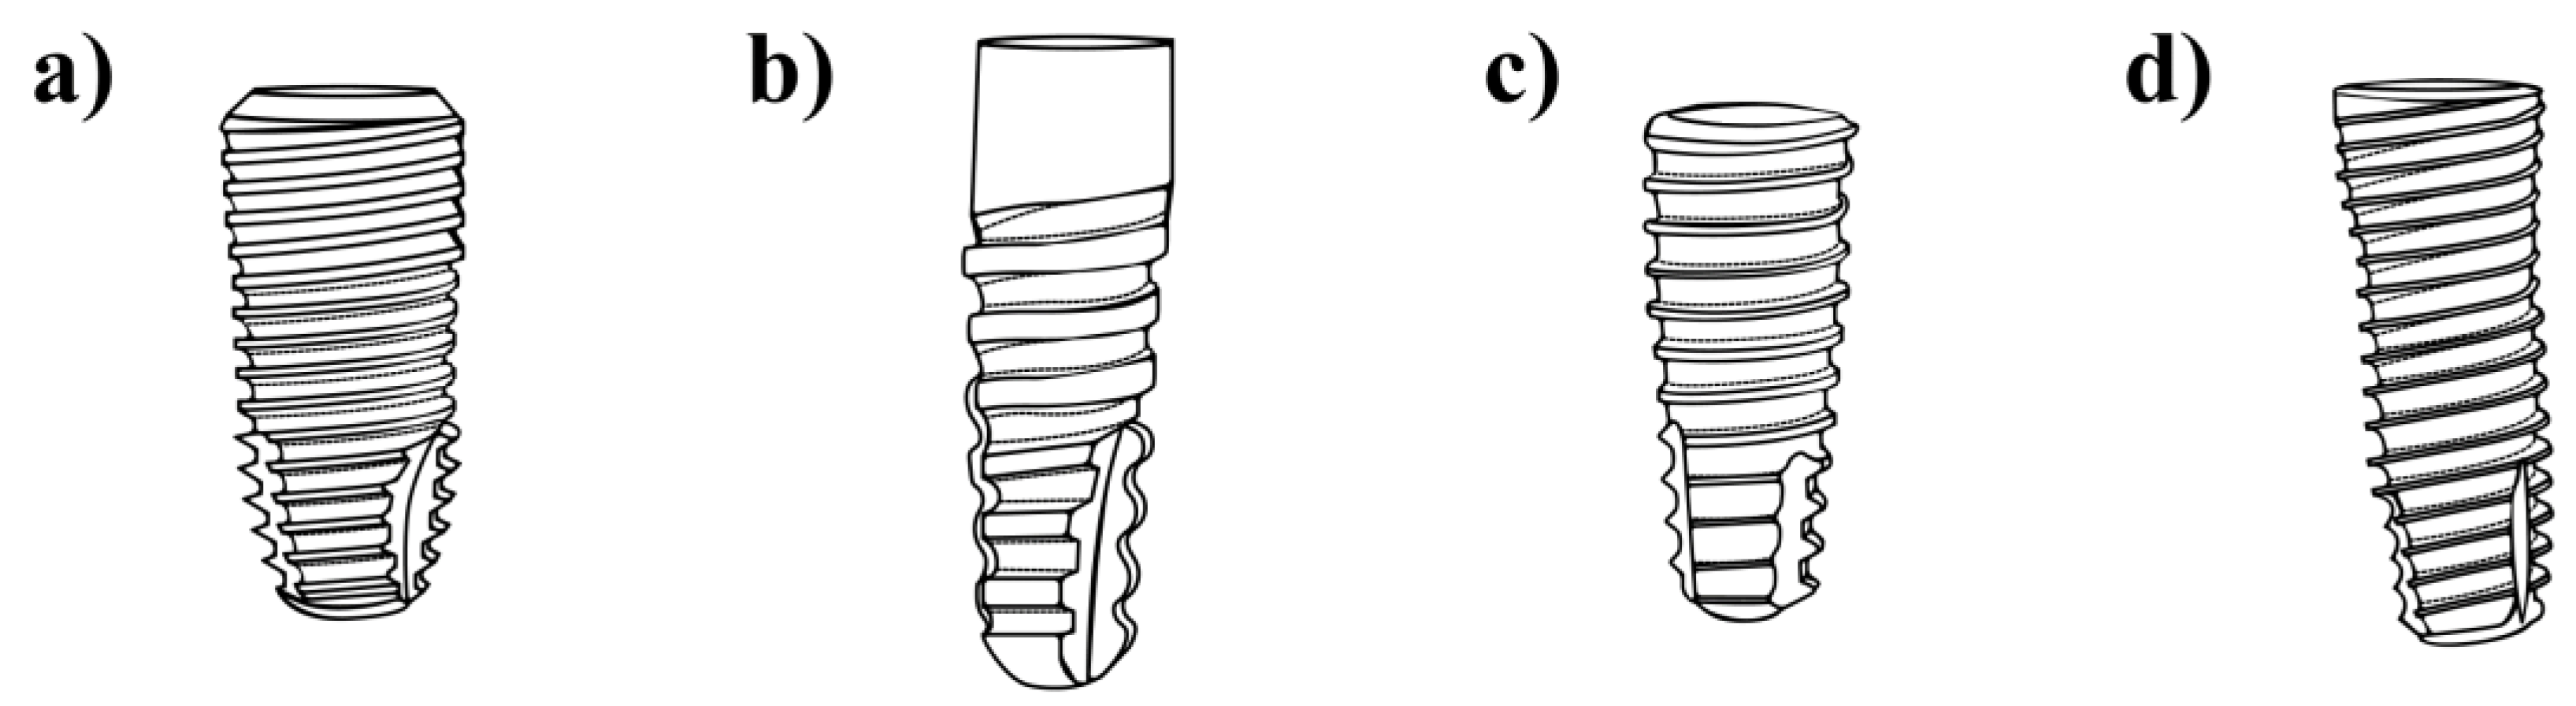

2.1. Materials

3.1. Dental Implants